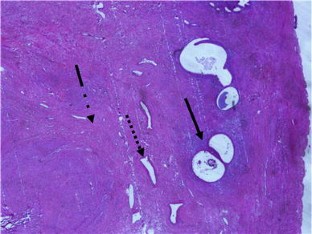

Total abdominal hysterectomy and bilateral salpingo-oopherectomy was performed and histologic examination revealed an adenomyoma arising primarily in the ovary.

Fig. 4